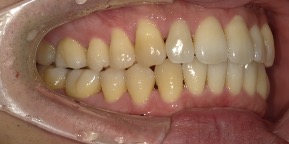

26歳女性のビフォーアフター

| 診断 | 空隙,叢生 |

| 治療方針 | 治療方針:前歯の咬合関係改善と空隙閉鎖を主な目的にて主にIPR(歯と歯の間をわずかに削合してスペースを獲得する方法)を組み込んだ動的矯正治療を行い、空隙、前歯咬合を改善後、保定を行う。臼歯部の咬合関係はプランの都合上維持することとした |

| 治療費 ※ | 69万8千円(診断、型取り、矯正中のメンテナンス、保定装置を含む料金) |

| 治療期間 | 1年8か月 |

| リスク | 1日20時間以上マウスピースを使用できない場合、歯が動かなかったり、想定しない誤差により不完全に終わる可能性がある。装着時や食事時に痛みを伴う。歯肉退縮や虫歯になるおそれがある。また、指導通りに装着できていない場合や適切なブラッシングが出来ていないとそのリスクが高くなる。歯根が短くなることがある。ごくまれに歯の神経が損傷してしまうことがある。過去にぶつけたり深い虫歯治療をしたことがあるとそのリスクはやや高くなる。矯正後には保定装置が必要。適切な使用ができない場合、後戻りの原因となる。将来的に歯並びが動いて再矯正が必要な場合がある。舌癖(舌で歯を押し出す癖)親知らずが正常に生えていない場合、その可能性がやや高くなる。 |